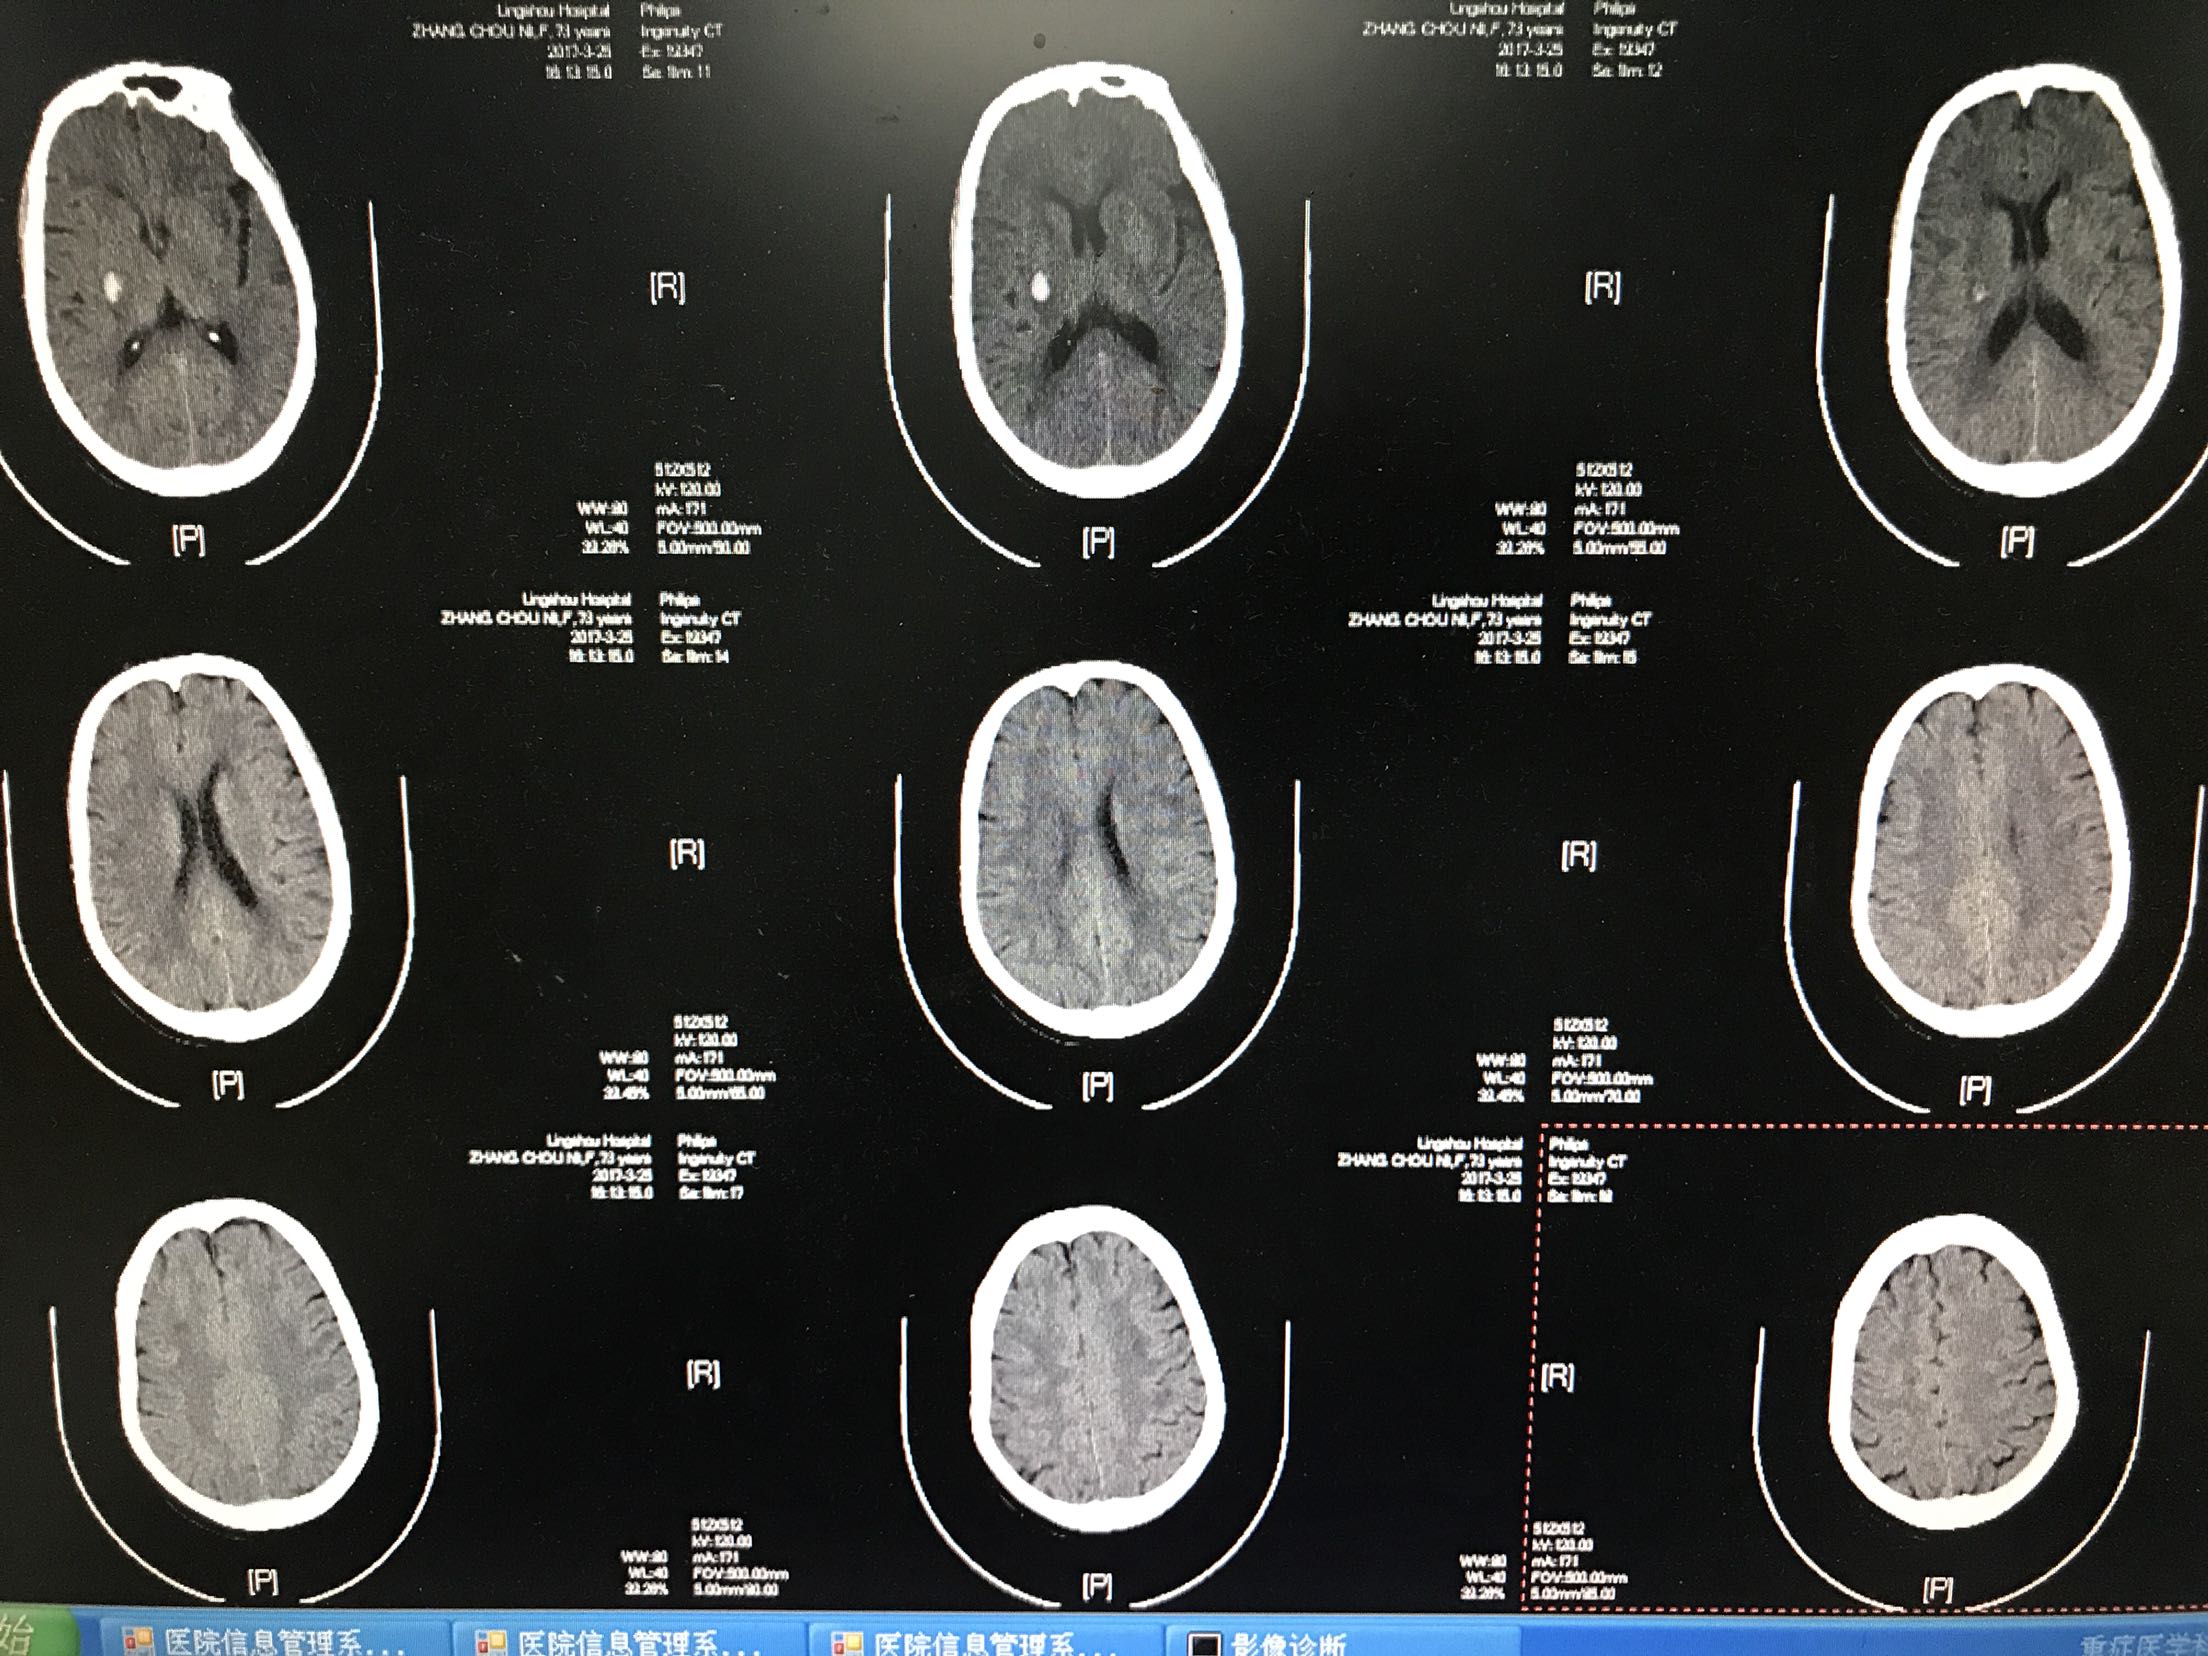

左侧肢体麻木无力1天入院,患者老年女性73岁,既往高血压病史8年,自服"得高宁",诉平时血压时高时低,"糖尿病"病史5年,平素口服"格华止和美吡达",自诉血糖控制可,否认其他病史!患者缘于1前天在家中做饭时出现左侧肢体麻木无力,左上肢尚可抬举,左下肢尚可负重,尚能独立行走,无头晕恶心呕吐,无复视及饮水呛咳,无明显言语功能障碍,无抽搐,当地卫生院考虑"脑梗死",给于"阿司匹林口服""丹红活血化瘀",及"低分子肝素钙抗凝",因病情无减轻,为进一步治疗来我院,查头Ct:1.右侧基底节脑出血2.双侧基底节,双额顶叶多发脑梗塞,为进一步治疗收住院

1.脑出血 2.高血压3级很高危 3.2型糖尿病 4.脑梗死,5.高脂血症,给予脑苷肌肽营养脑神经,白眉蛇毒血凝酶止血,甘露醇降颅压等对症支持治疗。

患者左侧肢体麻木逐渐好转,第2天复查头Ct血肿无扩大,7天复查头CT血肿淡染,高血压糖尿病,都是脑血管病的高危因素,可以导致动脉硬化,梗死和出血,本病人起初误诊为脑梗死,给予了不利于脑出血治疗的药物,可能加重病情,起病初期就应该及时查CT鉴别脑出血和脑梗死,避免误诊,应该吸取教训